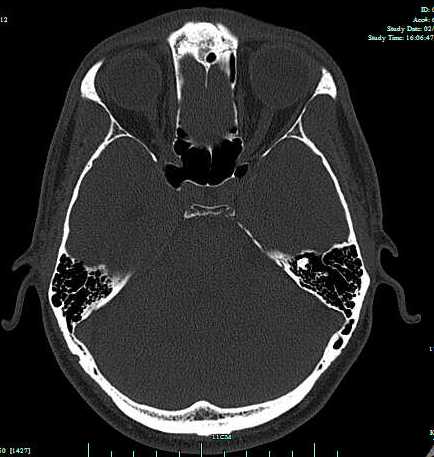

Ever wanted to get inside the head of a christian psychologist? Now you can explore the CAT scan images of a psychologist’s head courtesy of yours truly. Consider offering diagnoses and explanations as to how such an mind might work.

These images were taken to rule other matters that might be causing sinusitis. I found looking at my head both nerve wracking AND exciting at the same time.

Conclusion: Negative sinusitis. Nothing missing of note.